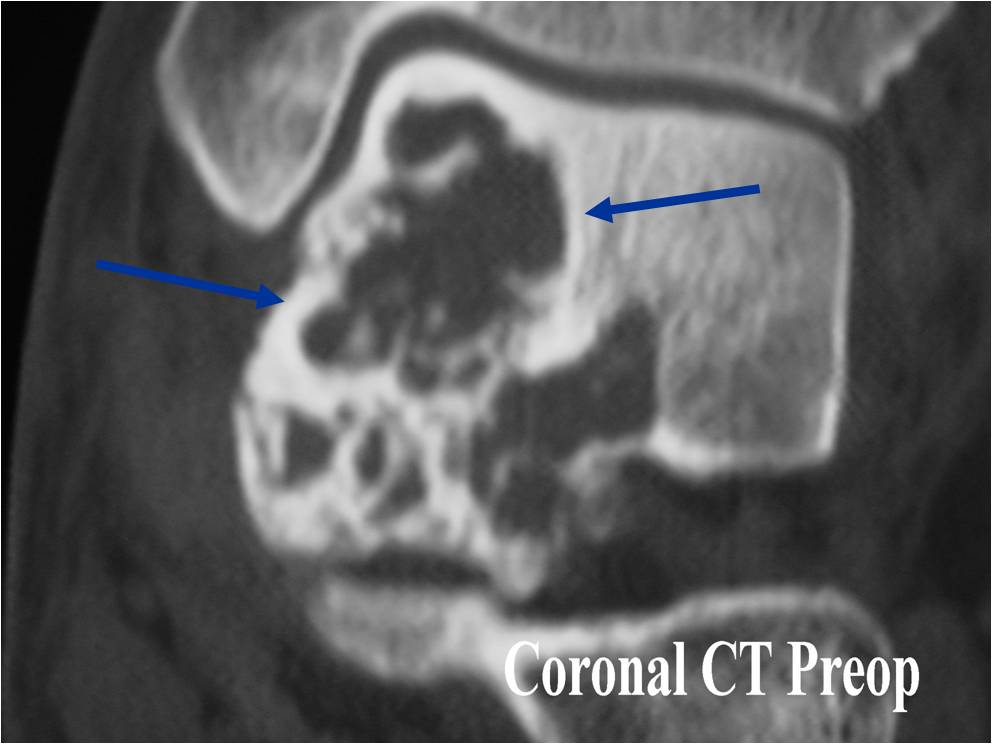

Radiographic Presentation

- Presents as a highly defined/well circumscribed geographic oval/round lytic defect

- Surrounded by rim of sclerotic bone

- Usually in epiphyseal region

- Lesion ranges from 3 cm to 6 cm diameter

- Usually radiolucent

- May have fine trabeculae and irregular calcifications

- Calcifications are often better detected with a CT scan but are not uniformly present

- Lesions may expand the bone and new periosteal bone may form

- Bony end plate, cortex, bone contour are unaffected

- (CT appearance)

- Most useful for detecting subtle mineralization not apparent on X-rays

- Useful for identifying intact periosteum around any expansile soft tissue component

- surrounding thin reactive shell of bone/mineralization (Egg Shell Rim of Calcification)

- helps place the tumor in a benign category

- helps evaluate:

- bony quality

- extent of bone and cortical destruction

- whether the subchondral plate of bone adjacent to the articular cartilage has been destroyed or is intact